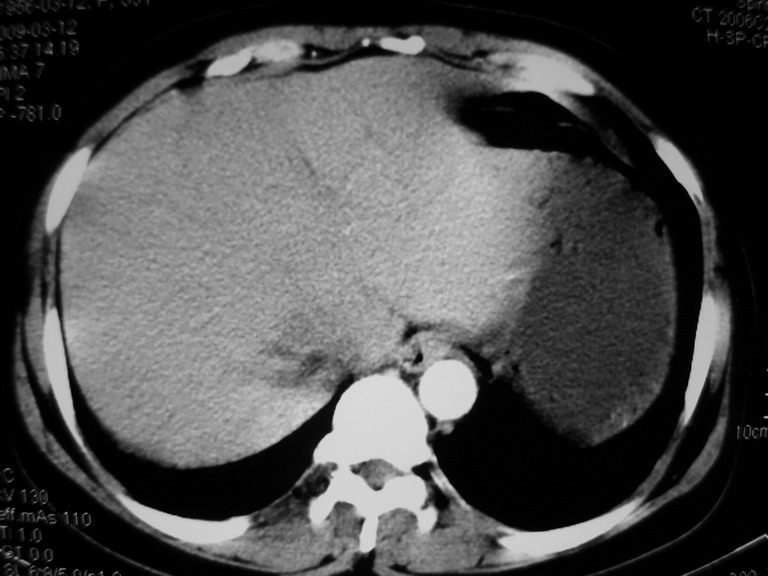

患者,女性50岁,上腹部不适2年余,既往多次腹部彩超未见异常,今日上午在我院查彩超发现肝右叶囊实性病变,外院辅助检查,afp,cea,ca199, 都在正常范围内,无肝炎史否认肿瘤史,生活在牧区

接着往下一贴看,有静脉期和延迟期,在看看和下腔静脉及十二指肠的关系,腔静脉内是不是栓子?

考虑肝右叶与尾叶交界区肝癌(部分外生),侵犯下腔静脉并下腔静脉瘤栓形成。

肝包虫病可能性大